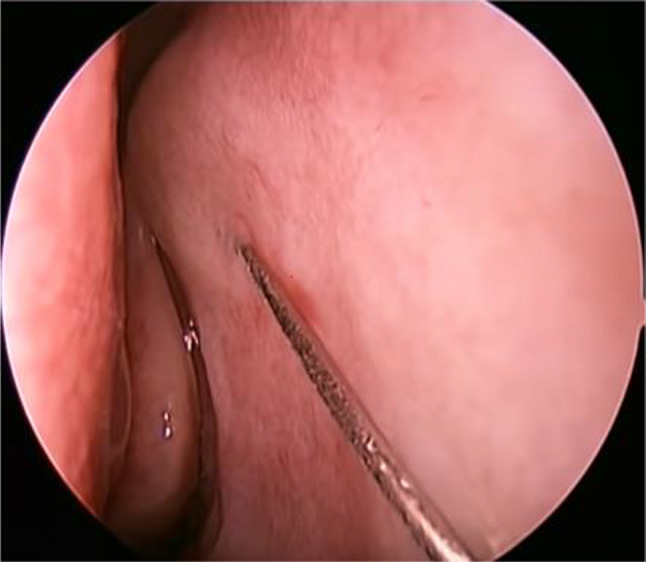

Packing and Infiltration: The nasal cavity was packed with 4% Xylocaine with 1:30,000 adrenaline half an hour before the start of operation. With the help of 0° 4 mm nasal endoscope, the area of the lateral wall of the nasal cavity like atrium, uncinate process and anterior part of the middle turbinate and adjacent part of the nasal septum was infiltrated with 2% Xylocaine with 1:80,000 adrenaline (Fig. 1).

Fig. 1.

Infiltration of the lateral nasal wall using 2% xylocaine with 1:80,000 adrenaline